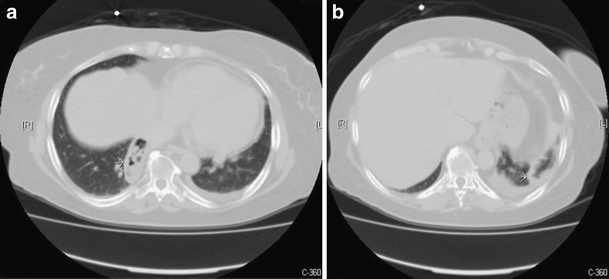

a CT scan of the upper abdomen at the time of the biopsy shows pleural effusion and perirenal hematoma (arrow). b CT scan of the upper abdomen shows homogeneous hypodensity in the spleen (arrow)